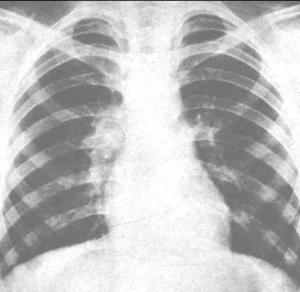

小儿原发型肺结核是原发性结核病中最常见者,为结核菌初次侵入肺部后发生的原发感染,是小儿肺结核的主要类型,占儿童各型肺结核总数的85.3%。原发型肺结核包括原发综合征和支气管淋巴结结核。前者由肺原发病灶、局部淋巴结病变和两者相连的淋巴管炎组成。后者以胸腔内肿大的淋巴结为主,而肺部原发病灶或因其范围较小,或被纵隔影掩盖,X线片无法查出,或原发病灶已经吸收,仅遗留局部肿大的淋巴结,故在临床上诊断为支气管淋巴结结核。此两者并为一型,即原发型肺结核。[1]